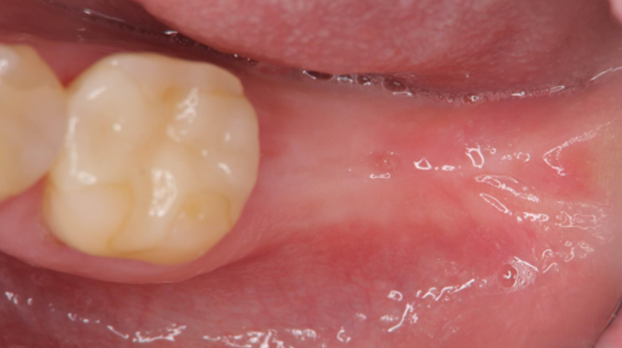

2. A follow-up examination was conducted three months after tooth extraction upon complete wound healing, and implant restoration was initiated.

Post-extraction wound healing status